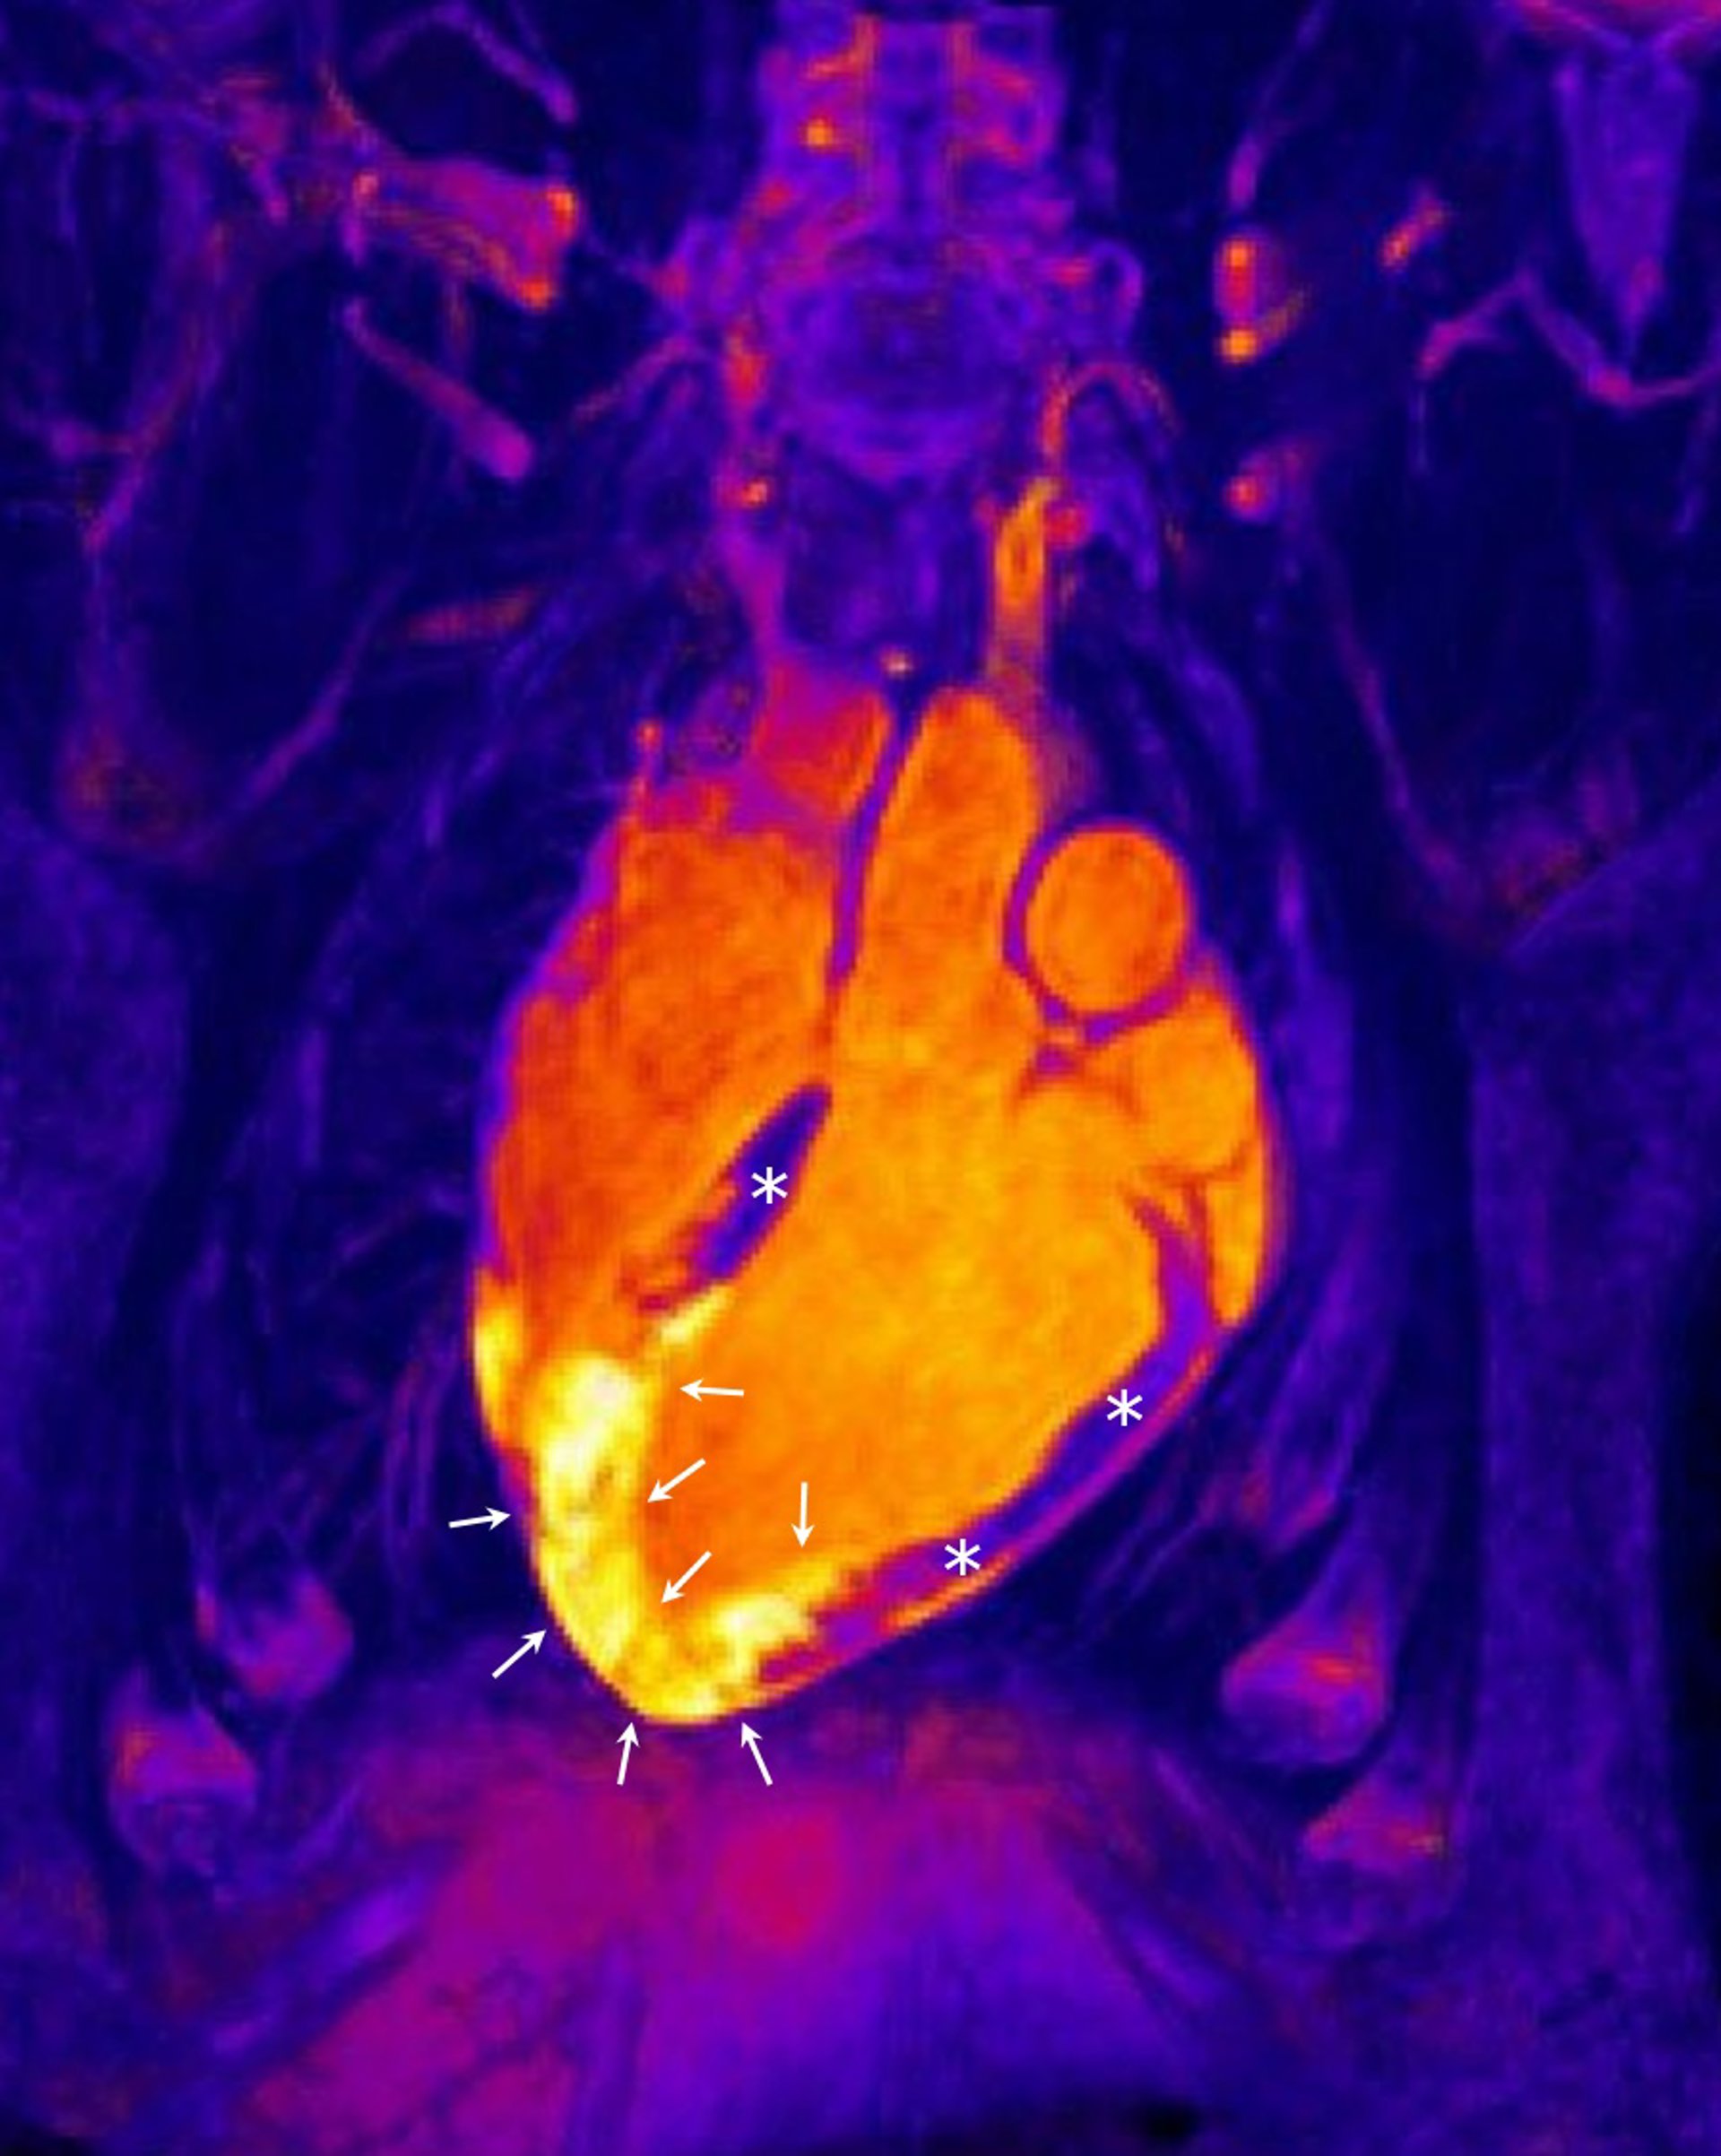

Corazón tras un infarto agudo de miocardio

Corazón tras un infarto agudo de miocardio - CNIC - Archivo